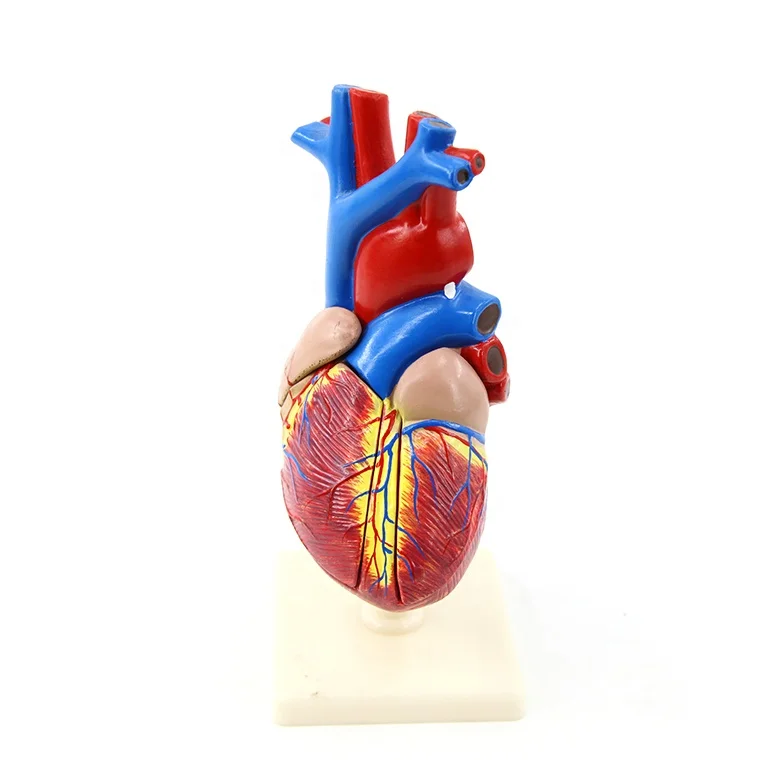

Valentine’s Day ช็อกโกแลตหัวใจ 12 ชิ้น – ของขวัญรังนกแท้ คอซซี่ โมเดลหัวใจมนุษย์ (Human Heart) | Shopee Thailand

โมเดลหัวใจมนุษย์ (Human Heart) | Shopee Thailand หัวใจมนุษย์ ภาพสต็อก – ดาวน์โหลดรูปภาพตอนนี้ – หัวใจ – อวัยวะภายใน …

ขยายกายวิภาคหัวใจมนุษย์รุ่น 3 ชิ้นส่วน – Buy กายวิภาคหัวใจ,หัวใจ … หัวใจมนุษย์ การออกแบบรายละเอียด ภาพประกอบสต็อก – ดาวน์โหลดรูปภาพตอนนี้ …

ForgetMeNot: Dessert strawberries with chocolate and cream | ช็อกโกแลต … ชีวิตพลาสติกกายวิภาคหัวใจมนุษย์รุ่น2ชิ้นส่วน – Buy การสอนรุ่น,Anatomy …

ชีวิตพลาสติกกายวิภาคหัวใจมนุษย์รุ่น2ชิ้นส่วน – Buy การสอนรุ่น,Anatomy … ช็อคโกแลตรูปหัวใจ [ภาพวาดฟรี] | OkusanPix

หัวใจวิทยาศาสตร์เรื่องกายวิภาคศาสตร์ทางการแพทย์หัวใจมนุษย์รุ่นขาย – Buy … รูปเวกเตอร์ฟรีหัวใจการ์ตูนปุ่ม PNG , หัวใจมนุษย์, หัวใจ, เซลล์ภาพ PNG …

ชีวิตพลาสติกกายวิภาคหัวใจมนุษย์รุ่น2ชิ้นส่วน – Buy การสอนรุ่น,Anatomy … ขนมช็อกโกแลตแท่ง ตรา โชกี้ โชกี้ 1 บาท แพ็ค 100 ชิ้น | Shopee Thailand

ขนมช็อกโกแลตแท่ง ตรา โชกี้ โชกี้ 1 บาท แพ็ค 100 ชิ้น | Shopee Thailand ชีวิตพลาสติกกายวิภาคหัวใจมนุษย์รุ่น2ชิ้นส่วน – Buy การสอนรุ่น,Anatomy …

ชีวิตพลาสติกกายวิภาคหัวใจมนุษย์รุ่น2ชิ้นส่วน – Buy การสอนรุ่น,Anatomy … รักสุดใจ! ช่อช็อกโกแลตให้เธอ รวมไอเดียช่อช็อกโกแลตสื่อรัก มอบให้แฟน

รักสุดใจ! ช่อช็อกโกแลตให้เธอ รวมไอเดียช่อช็อกโกแลตสื่อรัก มอบให้แฟน แบบจำลองหัวใจมนุษย์ขนาดชีวิตที่มีสีพื้นโปร่งใสโรคหัวใจทางการแพทย์แบบ …

แบบจำลองหัวใจมนุษย์ขนาดชีวิตที่มีสีพื้นโปร่งใสโรคหัวใจทางการแพทย์แบบ … Chocolate Heart, Hand-drawn sketch Chocolate s, brown, food png | PNGEgg

Chocolate Heart, Hand-drawn sketch Chocolate s, brown, food png | PNGEgg แบบจำลองหัวใจมนุษย์ขนาดชีวิตที่มีสีพื้นโปร่งใสโรคหัวใจทางการแพทย์แบบ …

แบบจำลองหัวใจมนุษย์ขนาดชีวิตที่มีสีพื้นโปร่งใสโรคหัวใจทางการแพทย์แบบ … ช็อกโกแลต รูปฟุตบอล เหรียญทอง หัวใจ บรรจุ 60 ชิ้น | Shopee Thailand

In-306 3d กายวิภาคศาสตร์หัวใจมนุษย์รูปแบบทางการแพทย์พลาสติกกายวิภาค … หัวใจมนุษย์ ภาพสต็อก – ดาวน์โหลดรูปภาพตอนนี้ – หัวใจ – อวัยวะภายใน, การ …

หัวใจวิทยาศาสตร์เรื่องกายวิภาคศาสตร์ทางการแพทย์หัวใจมนุษย์รุ่นขาย – Buy … หัวใจวิทยาศาสตร์เรื่องกายวิภาคศาสตร์ทางการแพทย์หัวใจมนุษย์รุ่นขาย – Buy …

หัวใจวิทยาศาสตร์เรื่องกายวิภาคศาสตร์ทางการแพทย์หัวใจมนุษย์รุ่นขาย – Buy … Anatomy หัวใจมนุษย์รุ่นพลาสติกทางการแพทย์กายวิภาคหัวใจจัมโบ้รุ่นอวัยวะ …

Anatomy หัวใจมนุษย์รุ่นพลาสติกทางการแพทย์กายวิภาคหัวใจจัมโบ้รุ่นอวัยวะ … รูปช็อกโกแลตหัวใจพร้อมน้ำเชื่อม PNG , วาเลนไทน์วัน, หัวใจ, วันแห่งความ …

3d Anatomy หัวใจมนุษย์รุ่นพลาสติกทางการแพทย์กายวิภาคหัวใจจัมโบ้รุ่น … หัวใจวิทยาศาสตร์เรื่องกายวิภาคศาสตร์ทางการแพทย์หัวใจมนุษย์รุ่นขาย – Buy …

หัวใจวิทยาศาสตร์เรื่องกายวิภาคศาสตร์ทางการแพทย์หัวใจมนุษย์รุ่นขาย – Buy … ส่งไว🚀24ชม. เจบีช็อกโกแลต รูปฟุตบอล เหรียญทอง เหรียญเงิน ทองแท่ง หัวใจ …

ส่งไว🚀24ชม. เจบีช็อกโกแลต รูปฟุตบอล เหรียญทอง เหรียญเงิน ทองแท่ง หัวใจ … Anatomy หัวใจมนุษย์รุ่นพลาสติกทางการแพทย์กายวิภาคหัวใจจัมโบ้รุ่นอวัยวะ …

Anatomy หัวใจมนุษย์รุ่นพลาสติกทางการแพทย์กายวิภาคหัวใจจัมโบ้รุ่นอวัยวะ … ภาพประกอบแบนเวกเตอร์หัวใจมนุษย์ขนาดใหญ่บนพื้นหลังสีขาว ภาพประกอบสต็อก …

หัวใจมนุษย์กายวิภาครุ่นวิทยาศาสตร์การแพทย์รูปแบบการสอน ห้องหัวใจมนุษย์: คำอธิบายโครงสร้างหน้าที่และประเภท

หุ่นจำลองหัวใจมนุษย์ 3d มนุษย์กายวิภาครุ่นหัวใจมนุษย์สำหรับซัพพลายเออร์แบบครบวงจรวิทยาศาสตร์ …

3d มนุษย์กายวิภาครุ่นหัวใจมนุษย์สำหรับซัพพลายเออร์แบบครบวงจรวิทยาศาสตร์ … 3d Anatomy หัวใจมนุษย์รุ่นพลาสติกทางการแพทย์กายวิภาคหัวใจจัมโบ้รุ่น …

3d Anatomy หัวใจมนุษย์รุ่นพลาสติกทางการแพทย์กายวิภาคหัวใจจัมโบ้รุ่น … อวัยวะหัวใจของมนุษย์ | องค์ประกอบกราฟฟิก แบบ PSD ดาวน์โหลดฟรี – Pikbest

หัวใจมนุษย์กายวิภาครุ่นวิทยาศาสตร์การแพทย์รูปแบบการสอน 15 Porch ช็อกโกแลต Fudge แม่พิมพ์ซิลิโคนหัวใจรูปเค้กช็อกโกแลตตกแต่ง DIY …

121,300+ หัวใจมนุษย์ ภาพถ่าย ภาพถ่ายสต็อก รูปภาพ และภาพปลอดค่าลิขสิทธิ์ … อุปกรณ์การศึกษากายวิภาคศาสตร์รุ่นหัวใจมนุษย์รุ่นสำหรับโรงเรียนขนาดชีวิต …

อุปกรณ์การศึกษากายวิภาคศาสตร์รุ่นหัวใจมนุษย์รุ่นสำหรับโรงเรียนขนาดชีวิต … วิธีทำ “นามะช็อกโกแลต” ของฝากยอดฮิตจากญี่ปุ่น อร่อยหรูดูแพง แต่ทำง่าย …

In-306 3d กายวิภาคศาสตร์หัวใจมนุษย์รูปแบบทางการแพทย์พลาสติกกายวิภาค … บอลลูนหัวใจมนุษย์ Angioplasty เวกเตอร์ ภาพประกอบ ภาพประกอบสต็อก – ดาวน์ …

The Heart หัวใจมนุษย์ 心脏 โรงงานโดยตรงขาย Anatomy หัวใจมนุษย์การฝึกอบรมชุดอวัยวะภายในรุ่น – Buy …

โรงงานโดยตรงขาย Anatomy หัวใจมนุษย์การฝึกอบรมชุดอวัยวะภายในรุ่น – Buy …